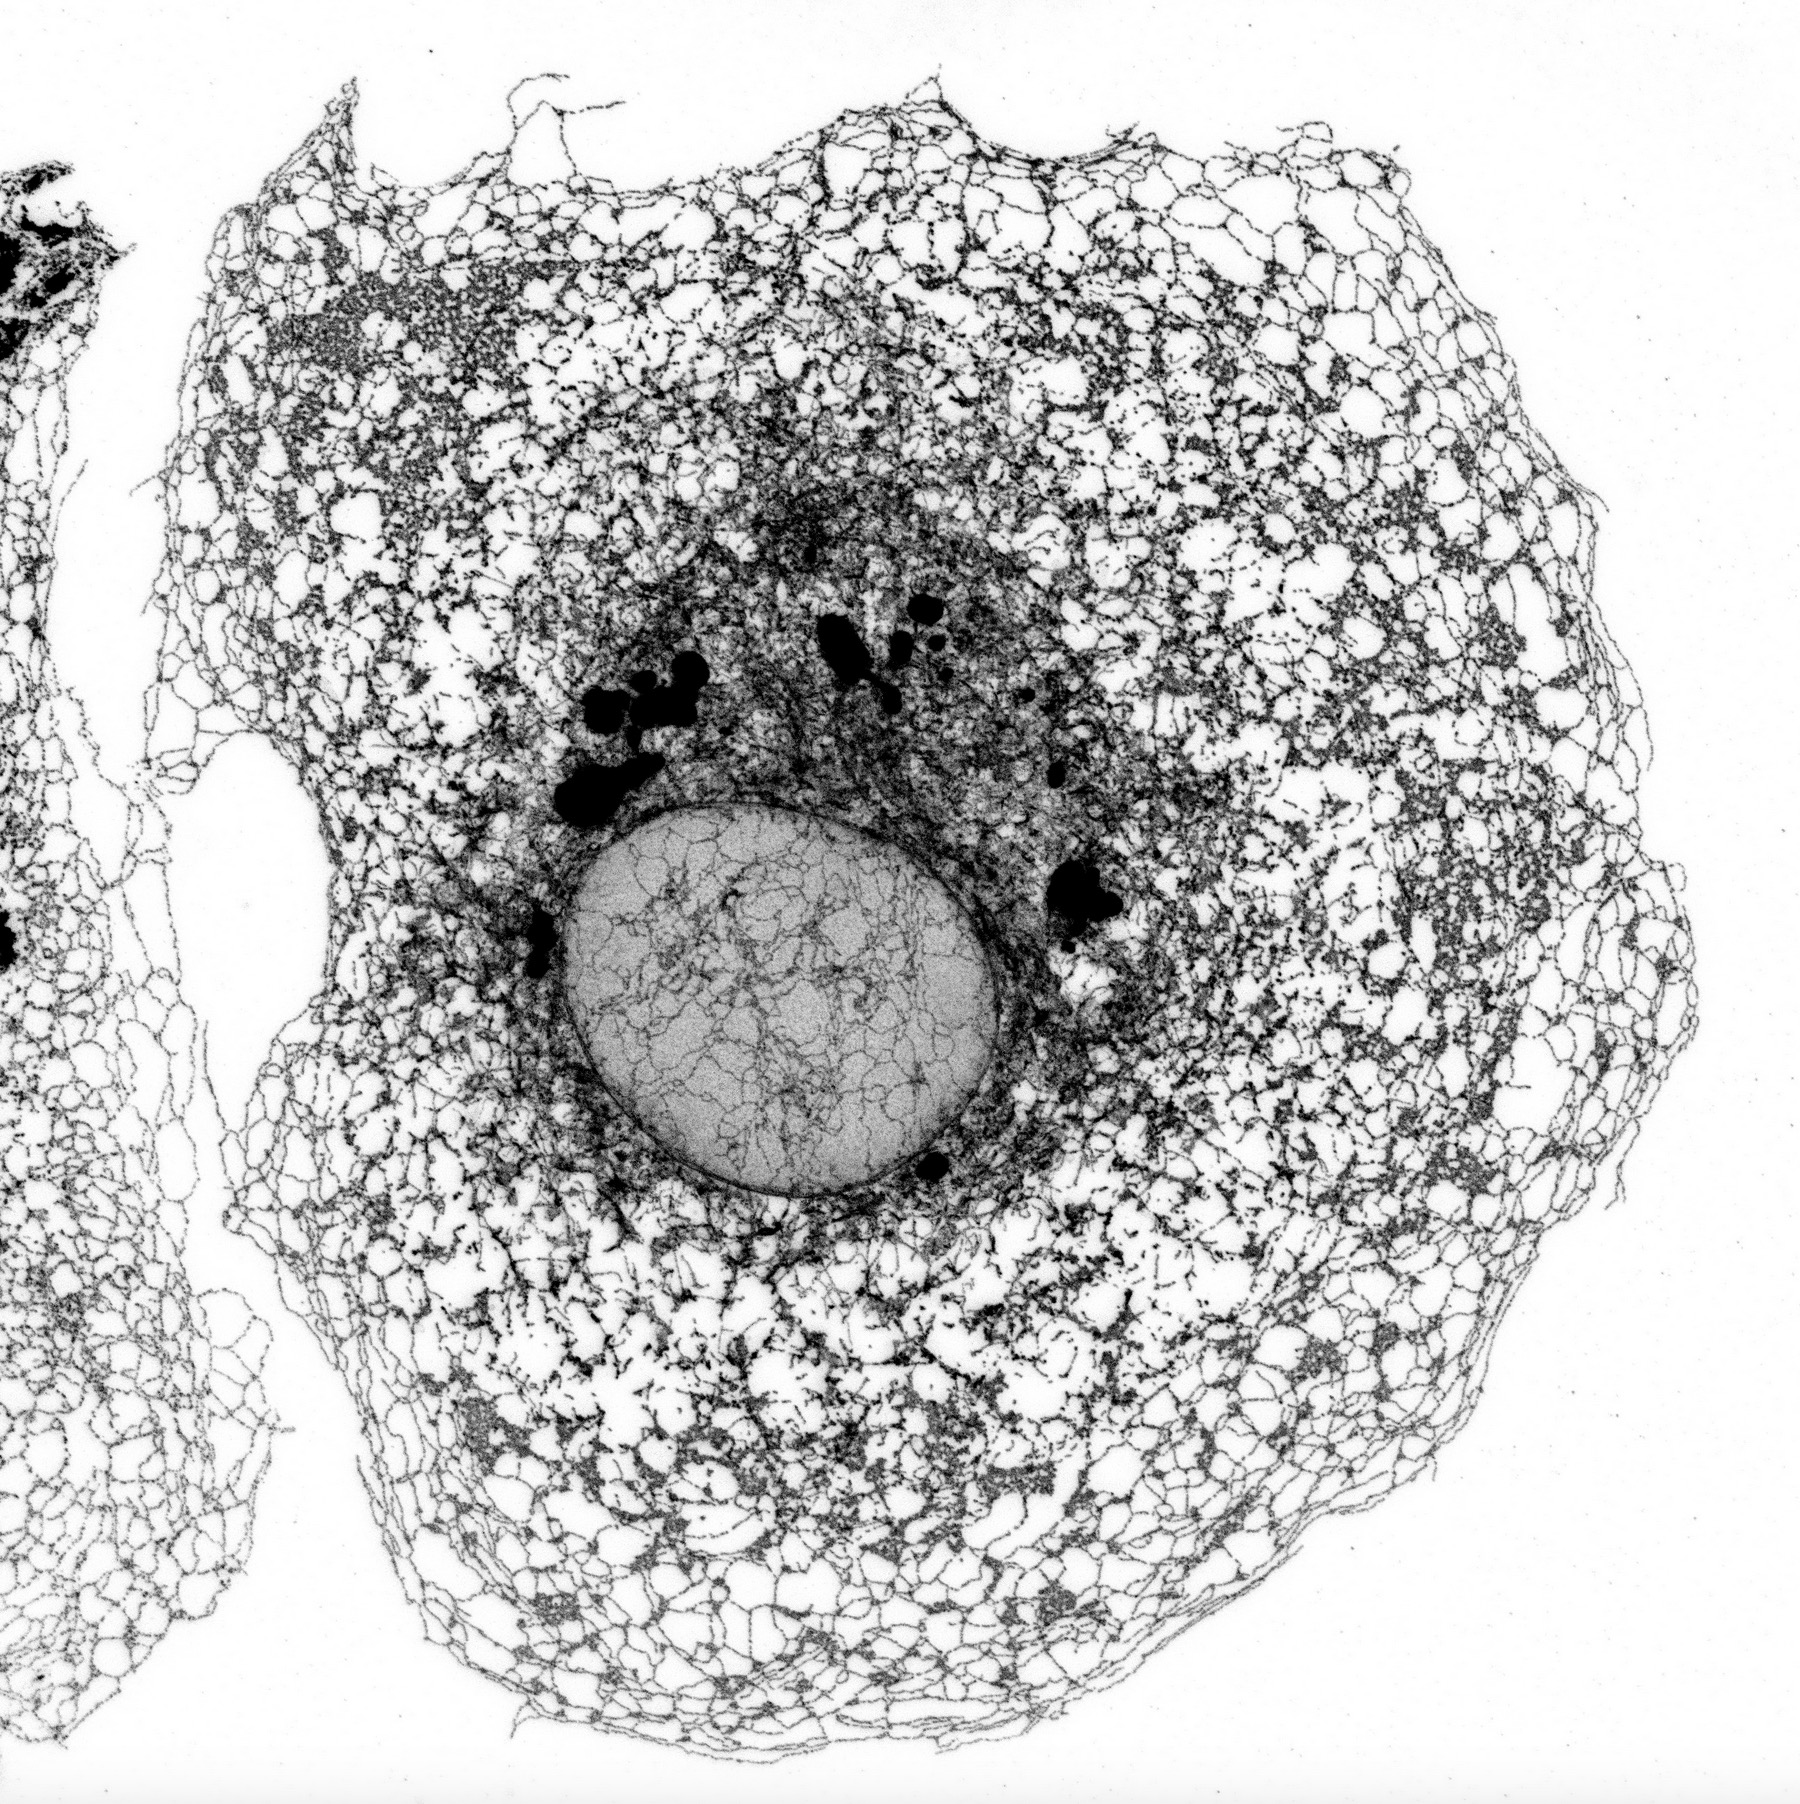

El retículo endoplásmico es una compleja red de membranas que realiza tareas esenciales, como la formación y maduración de al menos el 30% de las proteínas de la célula. La arquitectura de esta red de membranas debe adaptarse a la forma de cada tipo de célula, que puede variar según sean pequeñas, como linfocitos con forma esférica, o neuronas, con prolongaciones que llegan a medir varios centímetros. Además, el retículo endoplásmico debe ajustarse a las necesidades cambiantes de la célula y cuando no funciona en condiciones óptimas, una situación conocida como “estrés del retículo endoplásmico”, las células tienden a reestructurarlo y aumentar su volumen.

El control preciso de la arquitectura de esta red de membranas es crucial para la supervivencia y el correcto funcionamiento de los diferentes tipos de células en el organismo, pero aún se desconoce en gran medida cómo se lleva a cabo este control y cómo se coordina con los cambios en la forma de la célula.

Los investigadores utilizaron una metodología avanzada de microscopía de alto contenido (high-content microscopy), que permite capturar imágenes del retículo endoplásmico en cientos de miles de células y analizar su estructura de manera automatizada. Esto posibilita la realización, en tiempos razonables, de un cribado en el que se anula uno a uno la expresión de miles de genes para estudiar su impacto en la función celular.

El estudio reveló que una proteína de respuesta a estrés del retículo endoplásmico, PERK, desempeña un papel más amplio de lo que se pensaba anteriormente. No sólo limita la producción de nuevas proteínas cuando se activa por estrés del retículo endoplásmico, sino que también es esencial para que la expansión del retículo endoplásmico se acomode correctamente dentro del volumen celular.

“Uno de los primeros hallazgos inesperados de este estudio fue que cuando PERK se activa, no sólo reduce la síntesis de proteínas, sino que también relaja el anclaje entre el retículo endoplásmico y los microtúbulos del citoesqueleto (red de proteínas que organiza la forma de las células), permitiendo que el retículo endoplásmico se expanda y se distribuya de manera adecuada dentro de la célula”, explica Miguel Sánchez. Los microtúbulos implicados en el proceso de unión con el retículo endoplásmico son los denominados no centrosomales, y están relacionados con la orientación, organización y migración de las células de forma polarizada, en una dirección concreta.